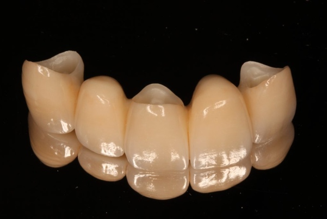

前歯を失ってしまった時、やはり歯がないまま過ごすのは辛いでしょうし、ブリッジであれば比較的早期に審美性を取り戻すことができます。またセラミック系のブリッジであればポンティック部分も歯肉と調和し、元あった歯以上に自然で美しい歯を作ることも可能です。

深く考えられた部分入れ歯の機能美もセラミックのブリッジの繊細な美しさも保険診療では設計や素材の制限から作ることはできず、治療費に関してはインプラント同様にかかってきてしまいます。